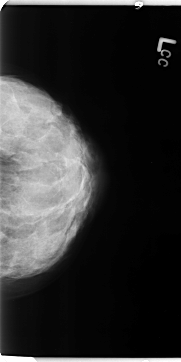

B_3112_1.LEFT_CC

LEFT_CC LINES 4704 PIXELS_PER_LINE 2352 BITS_PER_PIXEL 12 RESOLUTION 50 NON_OVERLAY